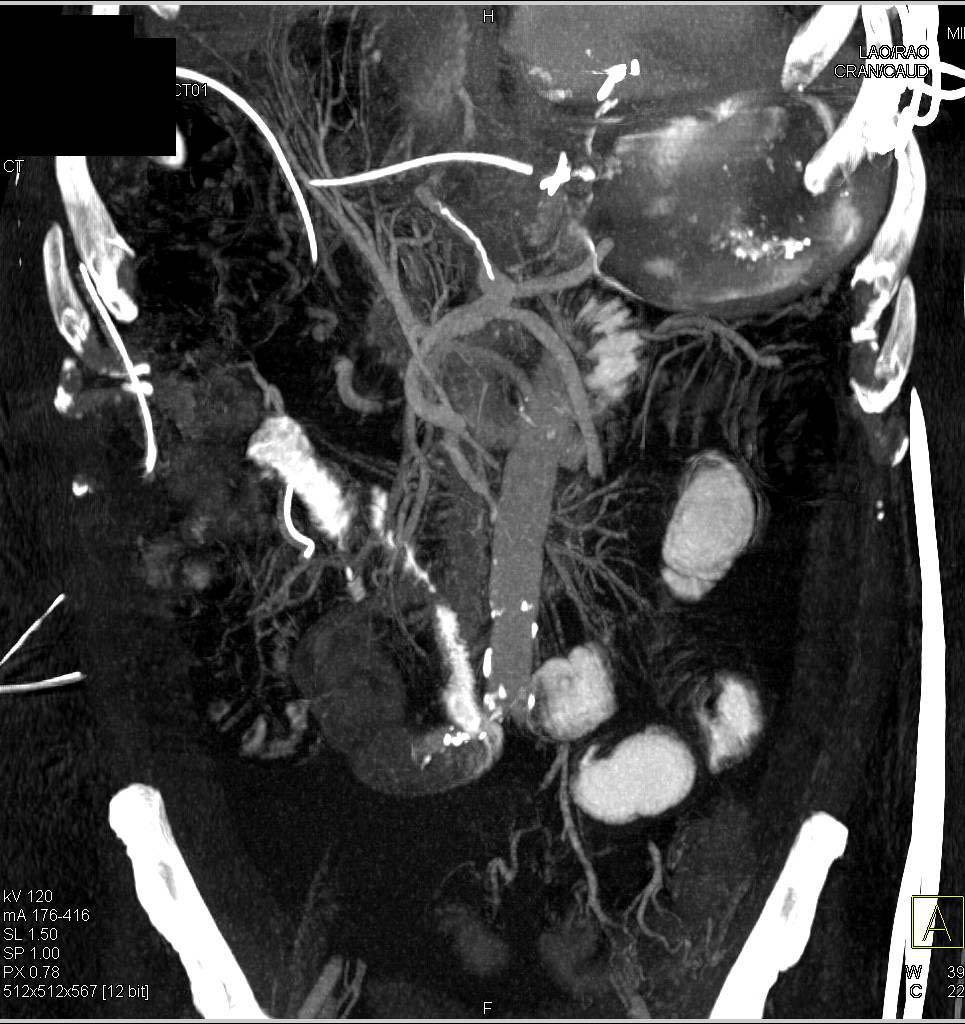

Gastric GIST Tumor